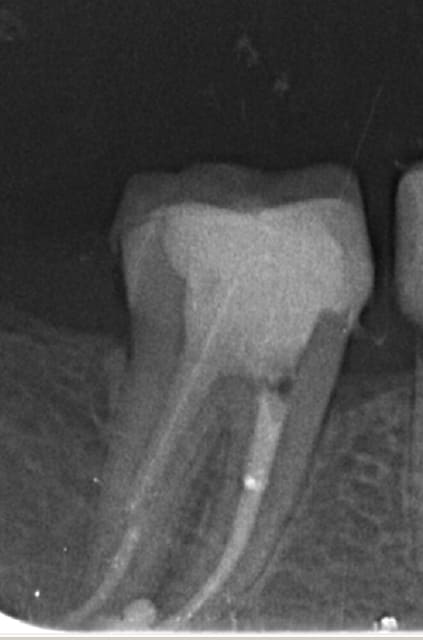

Je l'utilise de mieux en mieux mais c'est vrai qu'il y a une petite douleur ressentie par les patients. Je descend super bas, mais je vérifie que j'ai un bon tug back à chaque fois (je descends à 2-4 mm de l'apex), avec un 40 ou un 30 la plupart du temps.

Par contre sur les racines longues et fines j'ai aussi des patients qui se plaignent de douleurs lors de l'alésage, malgré des anesthésies de cheval, je ne comprends pas bien, je fais peri-apicale, intra-lig, et intra pulpaire, mais ils ont encore mal.

Endo 13  3  w39n8g - Eugenol

Endo 14  1  preop rl6qb9 - Eugenol

Endo 12  1  preop j7svi4 - Eugenol

Endo 13  1  preop sqffuc - Eugenol

Endo 13  2  ichn8i - Eugenol

Endo 14  2  fin bnbjik - Eugenol

Endo 15  1  preop vuyysh - Eugenol

Endo 15  2  l6mle4 - Eugenol

Endo 12  2  fin thdi3f - Eugenol